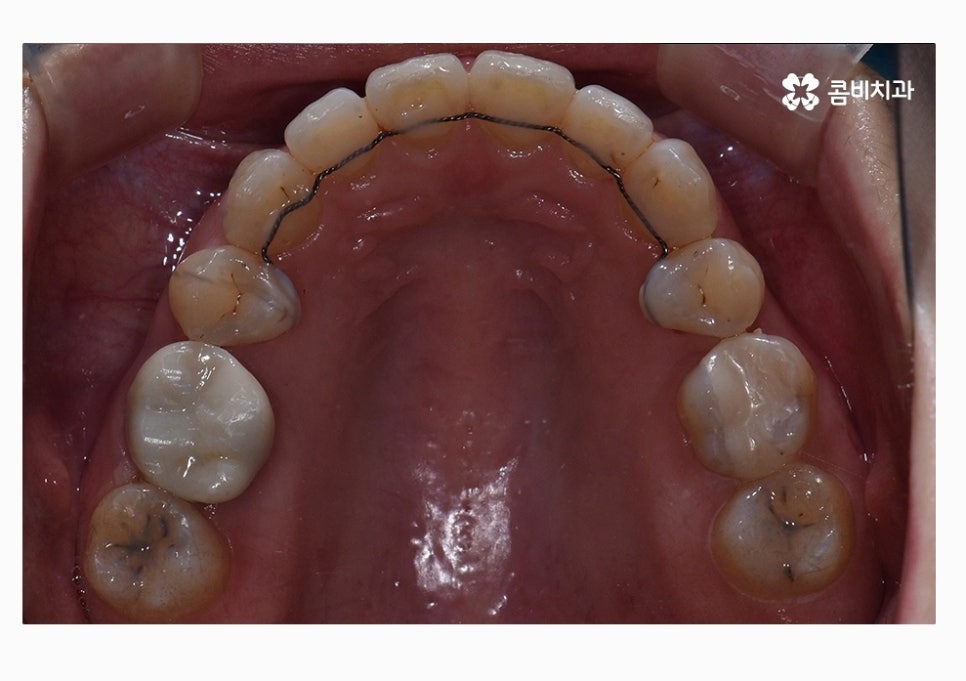

콤비교정은 윗니는 치아의 안쪽에 교정기를 부착하고

아랫니는 치아의 바깥쪽에 장치를 부착하는 방법으로

크게 웃지 않는다면 평소에는 잘 티가 안 나는

심미적으로 우수한 교정 방법이라고 할 수 있어요.

위 환자분의 경우에는 콤비교정의 치료 경과를 보면

아랫니가 정상교합이 되었고 치열도 보다 가지런하게

변화되고 있음을 알 수 있는데요.

콤비교정을 선택하시는 분들 중에서는 이처럼 치열과 함께

부정교합을 개선하고자 하시면서 직업적인 이유 등으로

교정 장치가 잘 보이지 않길 원하시는 분들에게 선호되고 있어요.